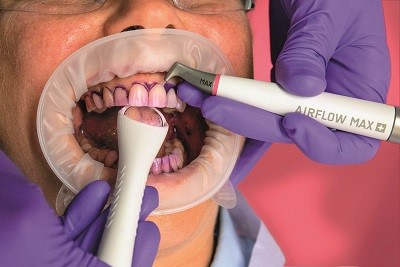

Идеальное удаление наддесневой и поддесневой биопленки со всех поверхностей зубов можно достичь только с помощью технологий AIRFLOW®/PERIOFLOW® и AIRFLOW® С ПОРОШКОМ РLUS (рис. 4).

Рис. 4. Исользование Airflow MAX для удаления биопленки

Преимущества перед классической процедурой (полирование с помощью резиновых чашечек) включают в себя:11 полное удаление биопленки из фиссур, полостей, с поверхностей имплантатов, в межзубных пространствах, в местах скученности зубов, в пришеечной зоне, с поверхностей несъемных ортодонтических аппаратов, и все это без какого-либо повреждения природной структуры зубов. Обеспечивается гораздо менее агрессивное воздействие при обработке оголенных шеек зубов. Удаляется приблизительно в три раза больше биоплёнки с поддесневых поверхностей, чем с помощью ручных инструментов.12

Дополнительные преимущества: сокращенное время процедуры лечения, максимальный комфорт для стоматолога и пациента, влияющий на улучшение восприятия процедуры пациентом и, как результат, высокий показатель повторных визитов.

Примечание: Чтобы успешно устранять наддесневую и поддесневую биопленку и при этом эффективно уменьшить формирование пылевого и аэрозольного облака, необходимо следовать рекомендациям по надлежащему использованию AIRFLOW® и аспирационного оборудования. Новейший наконечник AIRFLOW® Max с технологией ламинарного потока генерирует меньше аэрозоля.